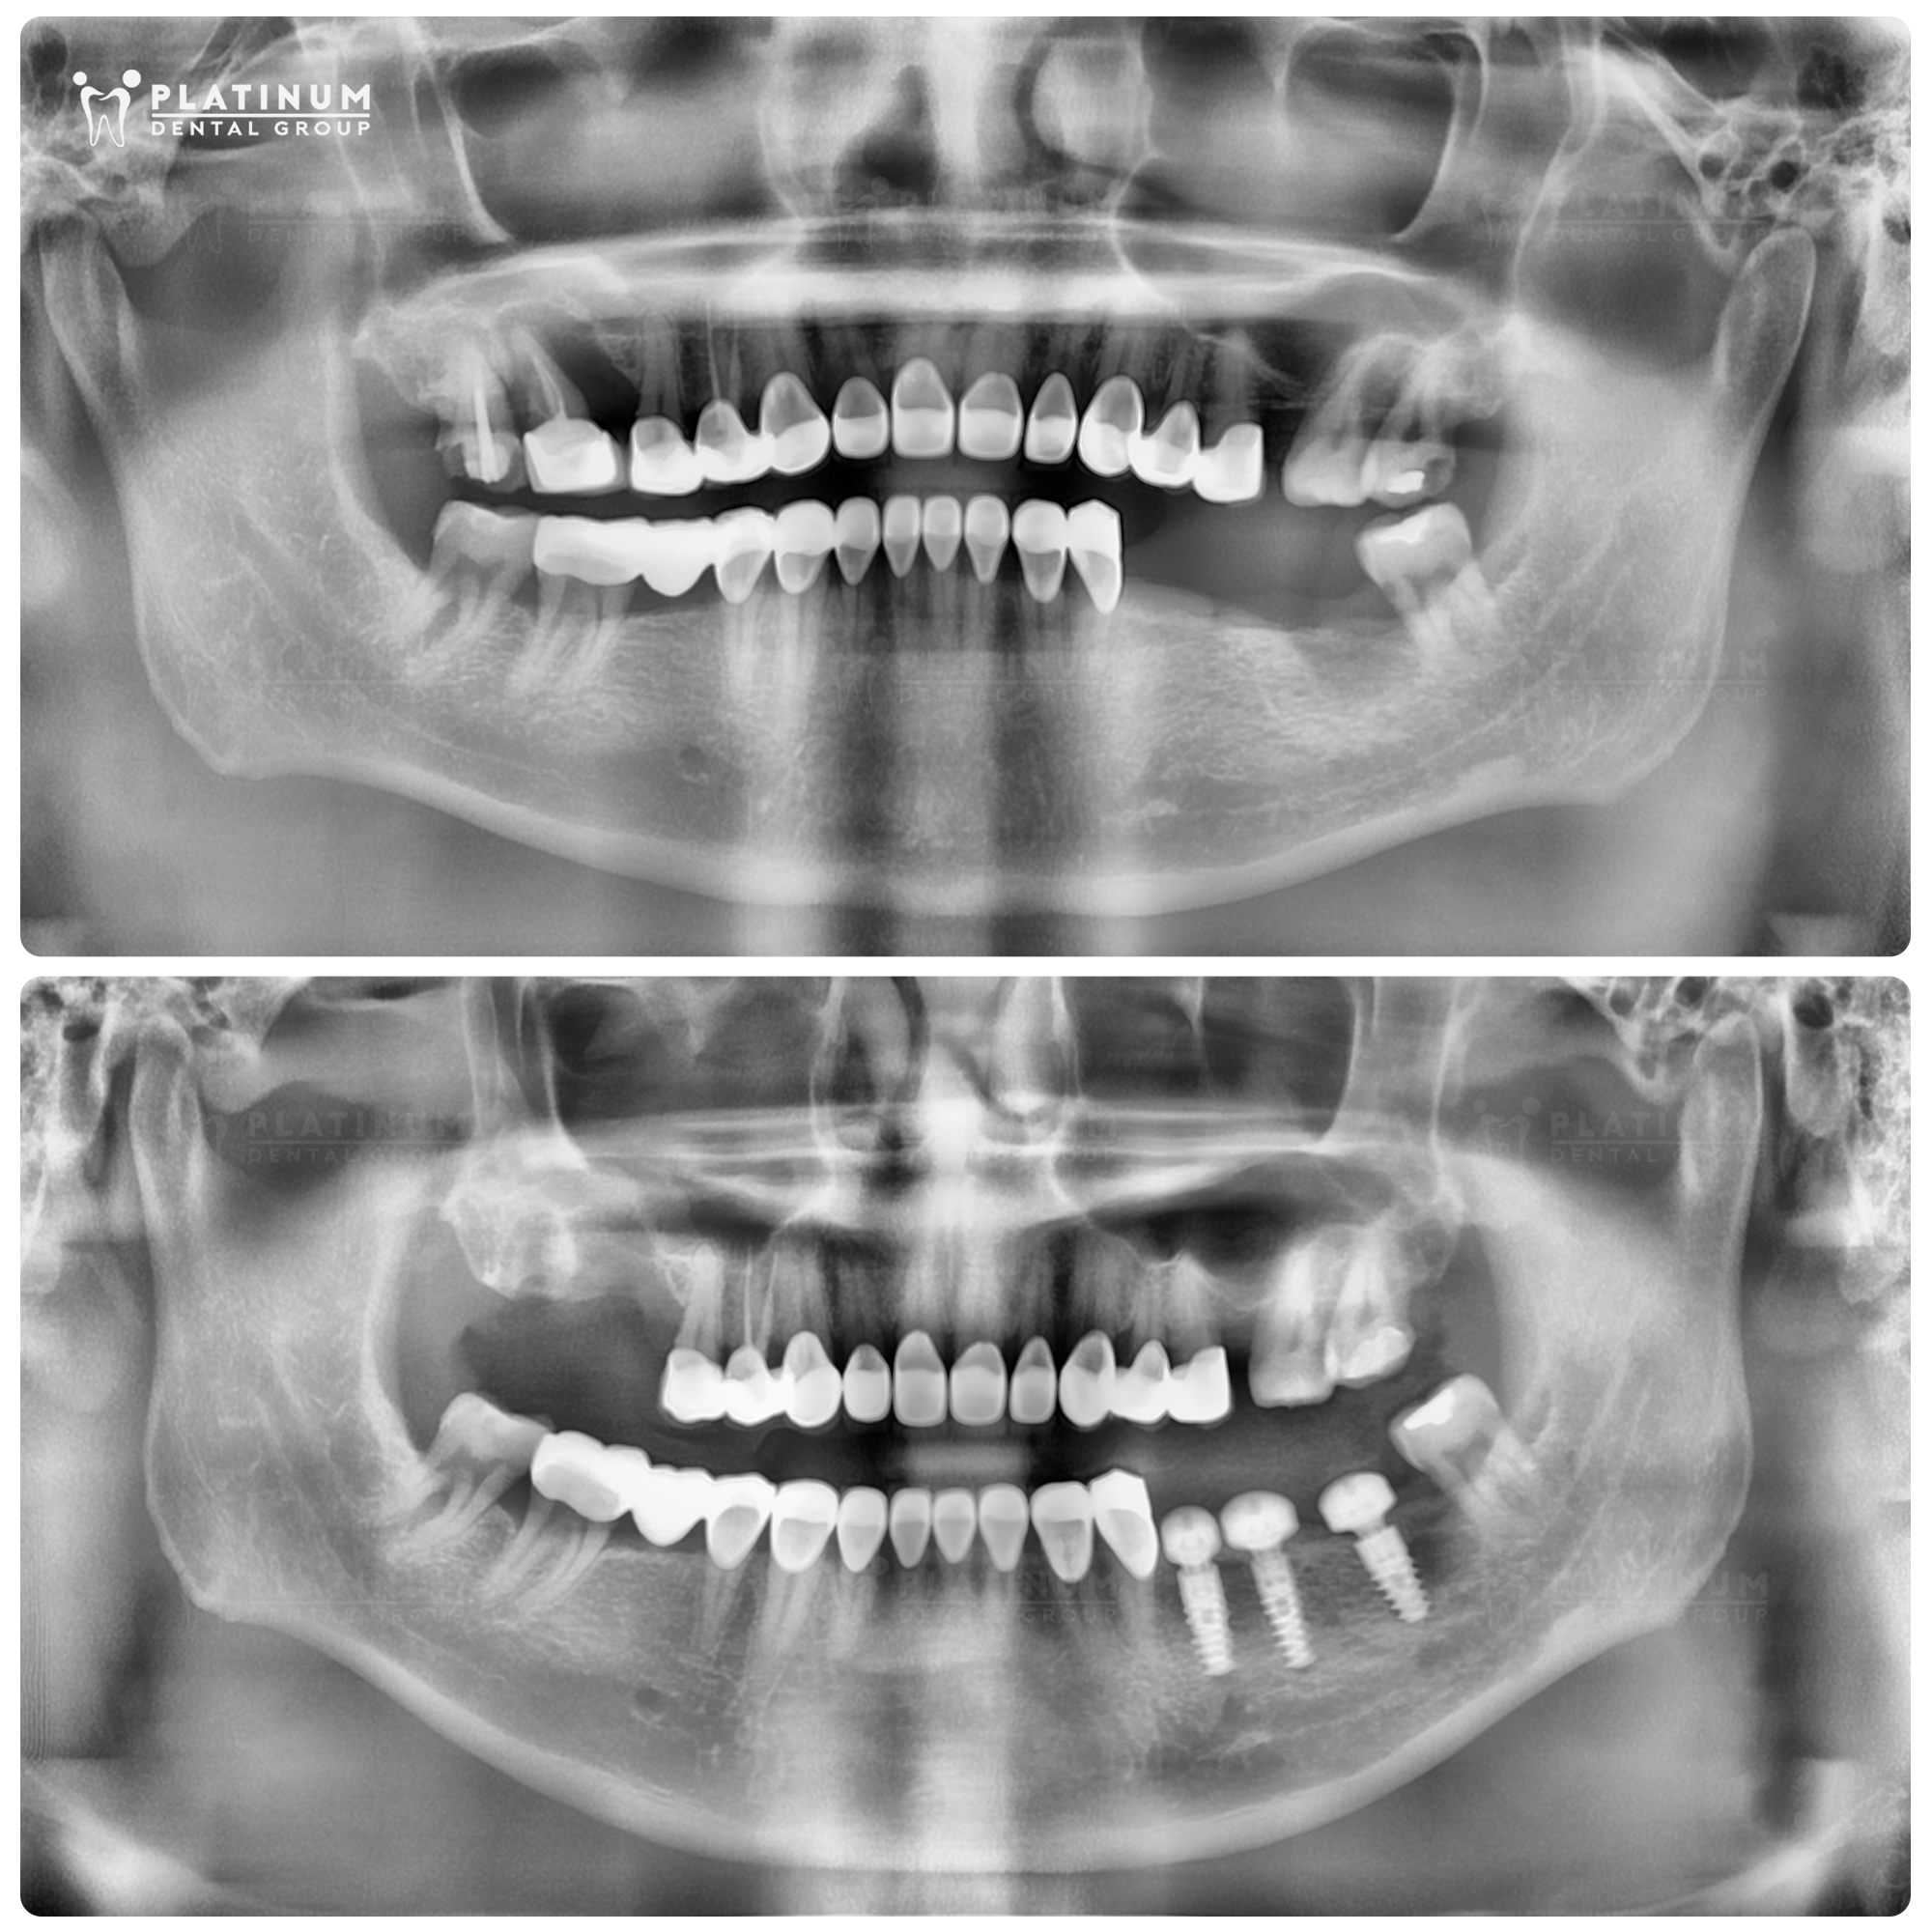

Hình ảnh trước và ngay sau cấy ghép Implant của anh Sơn.

Từng chần chừ vì sợ đau và e ngại chất lượng điều trị, anh Lâm Sơn (50 tuổi, TPHCM) chỉ quyết định trồng răng khi được bác sĩ tư vấn rằng việc trì hoãn có thể khiến xương hàm tại vùng răng mất bị tiêu, làm ca cấy ghép phức tạp hơn. Tin tưởng vào kinh nghiệm của ThS.BS Dương Minh Tùng cùng việc ứng dụng các công nghệ nha khoa hiện đại tại Platinum Dental Group, anh đã bắt đầu điều trị và khôi phục thành công 3 răng hàm với trải nghiệm nhẹ nhàng hơn so với lo lắng ban đầu.